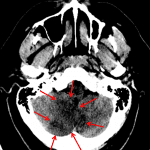

- Areas of hypodensity and loss of gray-white differentiation in the medial right greater than left cerebellar hemispheres

- Hyperdense appearance of the intradural right vertebral artery

Areas of hypodensity and loss of gray-white differentiation in the medial right greater than left cerebellar hemispheres, consistent with acute/early subacute PICA territory infarcts. No significant mass effect or evidence of hemorrhagic transformation.

Hyperdense appearance of the intradural right vertebral artery, suggesting the presence of thrombus.